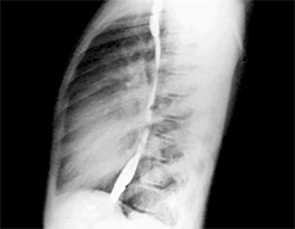

PA and Lateral

Click on the Xrays to enlarge them.